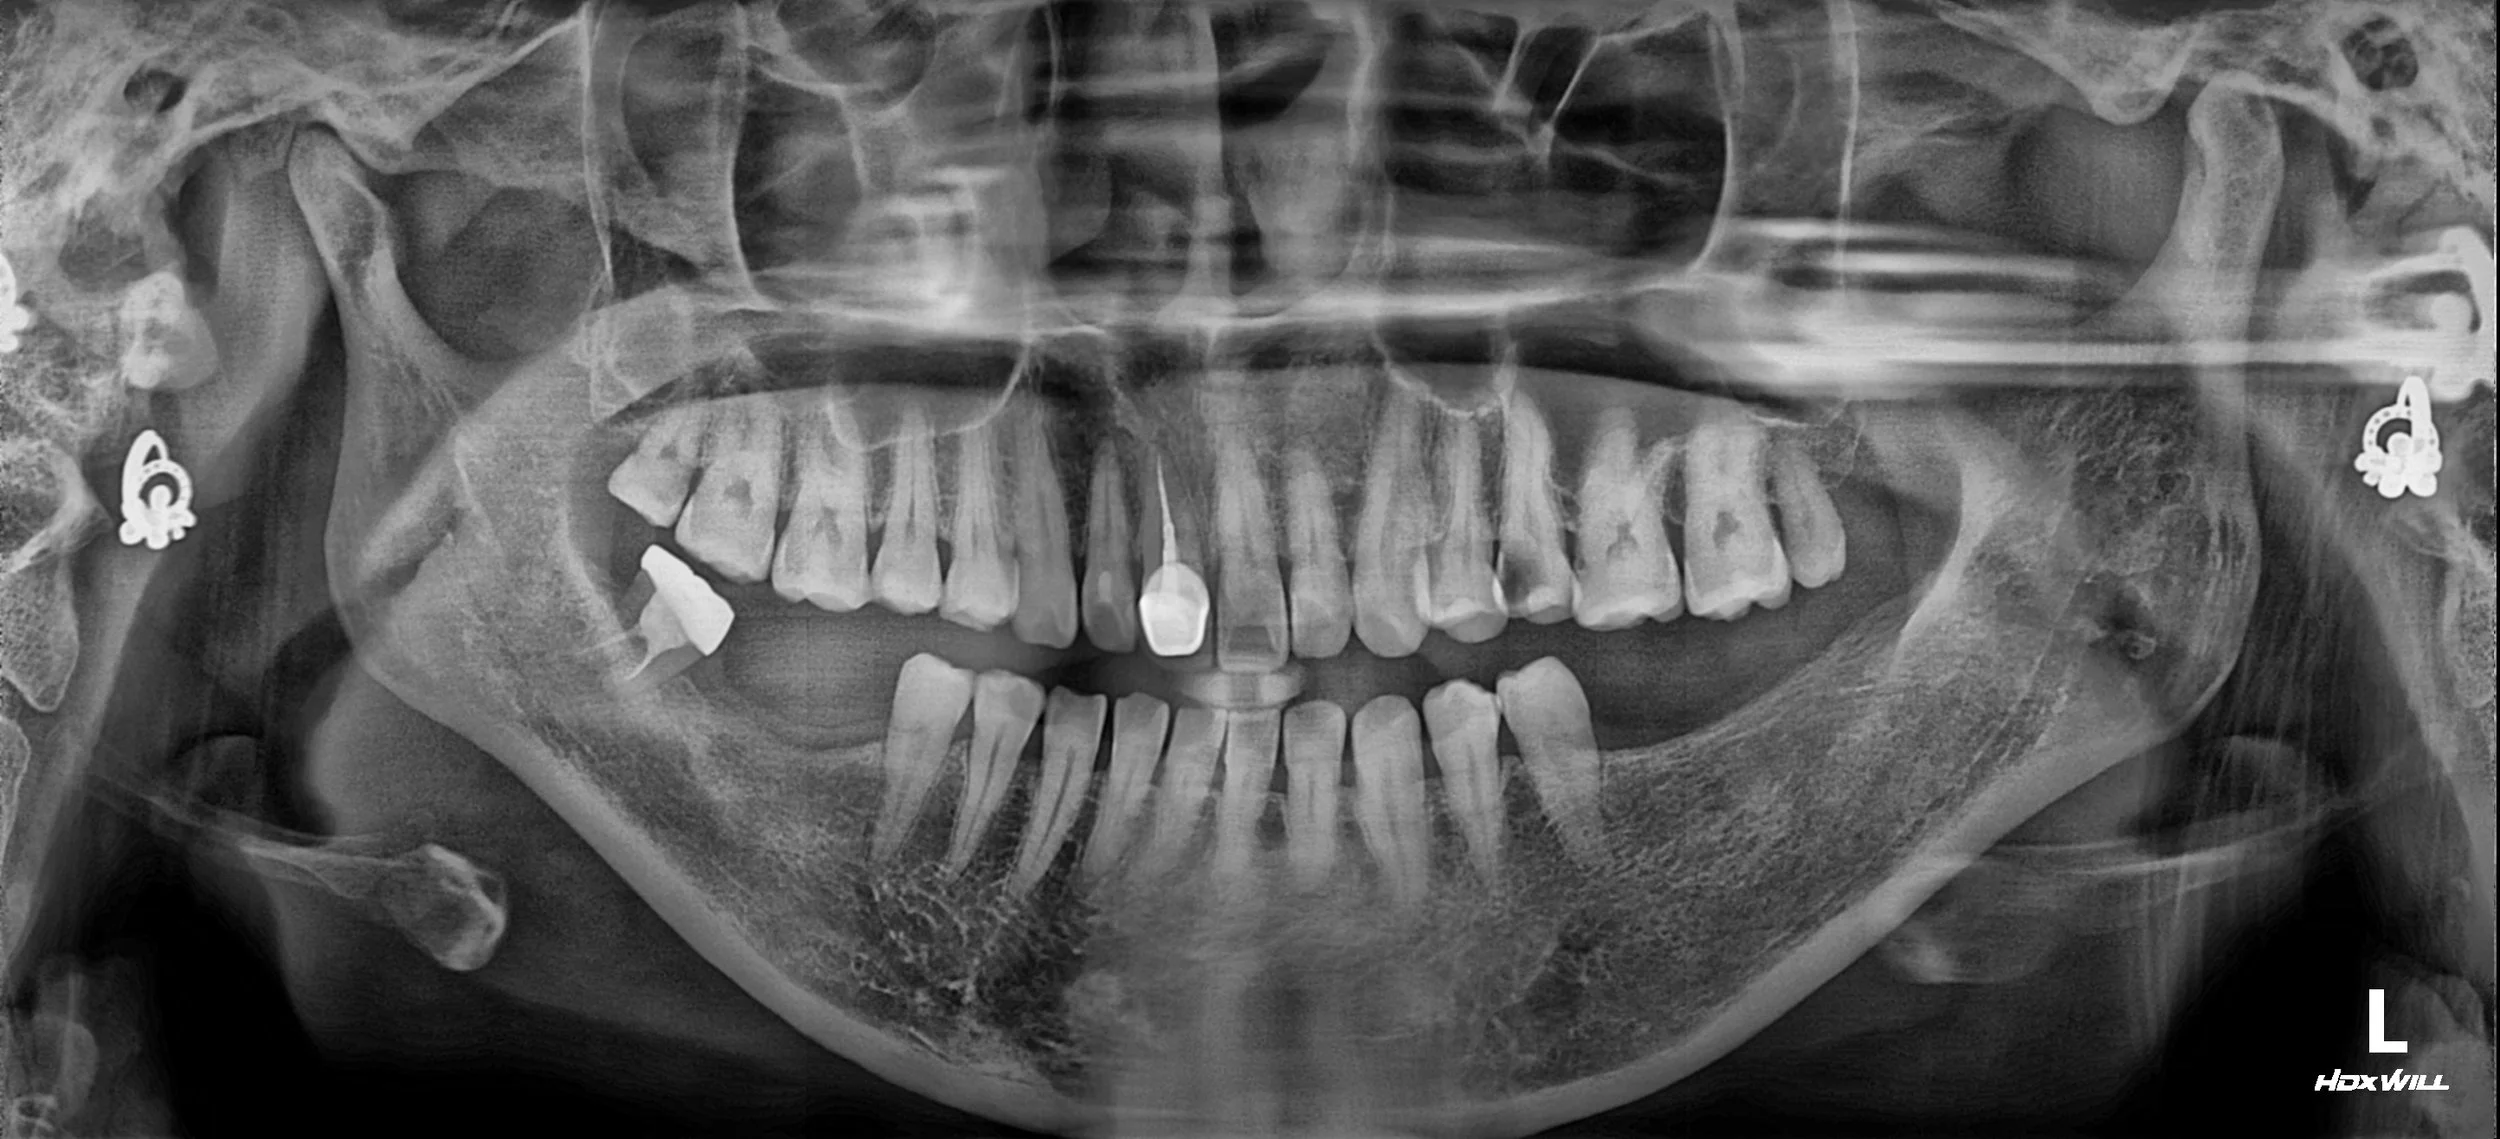

29. Full Mouth Rehabilitation: Restoring Mandibular Position and Occlusal Balance

Correction of Mandibular Retrusion and Anterior Flaring in a Male Patient in his 50s. Re-establishing a predictable balance of forces through posterior implants and non-prep veneers.